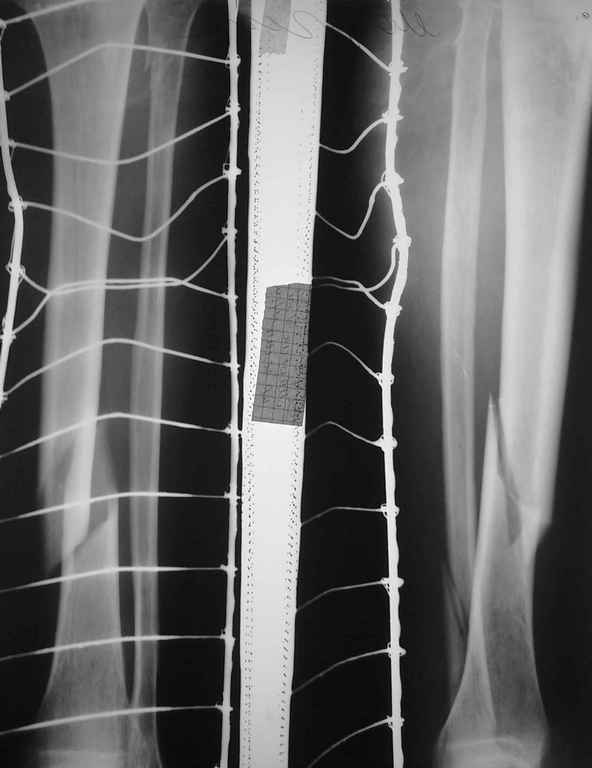

Необходим Ваш совет относительно тактики лечения пациента В.50 лет с

распространенным псориазом (болеет ок.20 лет) и данным видом перелома.

Предполагалось произвести БИОС, однако сопутствующая патология, по

утверждению ряда коллег, является противопоказанием к оперативному

лечению.